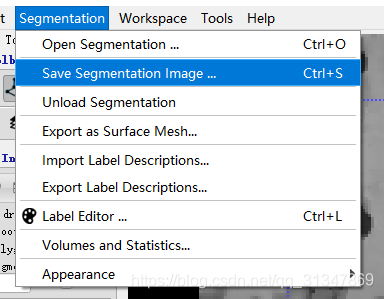

保存分割结果:

Segementation -> Save Segmentation Image

SNAP 将分割结果保存为图片,voxel 在图像中保存为 0 ~ 255,分割结果可保存为不同的格式以便其他程序读取